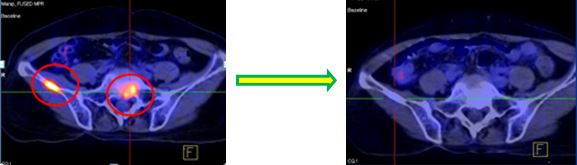

Hình ảnh PET/CT trước và sau 6 chu kỳ điều trị với Cisplatin-Pemetrexed

Trước điều trị: U phế quản gốc phải, kích thước: 1,6x2,9cm, Max SUV=5,76 | Sau điều trị: U tan hết, không còn tổ chức tăng hấp thu FDG |

Trước điều trị: Hạch cạnh phải khí quản KT 1,2x2,0 cm, Max SUV=5,08 | Sau điều trị: Hạch cạnh phải khí quản tan hết |

Trước điều trị: - Đau xương chậu nhiều - Tổn thương xương cánh chậu phải max SUV=5,34 - Tổn thương xương cùng S1, Max SUV=4,4 | Sau điều trị: - Không đau xương - Không còn tổn thương di căn xương

Sau 6 chu kỳ điều trị hóa chất, bệnh nhân được điều trị duy trì liên tục bằng Pemetrexed. Hiện tại bệnh ổn định 20 tháng, đã điều trị duy trì 12 đợt Pemetrexed. Trên lâm sàng bệnh ổn định, không khó thở, không ho, tăng cân, thể trạng tốt lên. Tác dụng phụ ở mức độ nhẹ: mệt mỏi, buồn nôn. Chụp PET/CT: u, hạch, di căn xương tan biến.